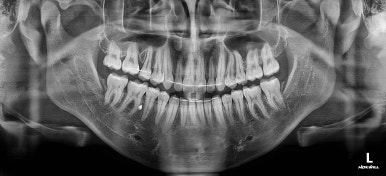

이제 전후 비교를 해볼게요.

1년 7개월 만에 매우 고난이도의 치료를 임플란트 없이 사랑니까지 당겨와서 사용한 만족스러운 치료였습니다.

우측의 결손치아보다 뒤쪽에 있는 치아는 크기나 모양이 원래의 큰 어금니보다 작고 다르게 생겨서 100% 이상적인 교합을 얻기는 한계가 있었어요.

하지만 임플란트 없이 충분히 가능할 수 있게끔 해주어서 환자분도 매우 만족하는 치료가 되었어요.

뿌리도 남아있었고 골 결손도 심했던터라 뒤쪽 치아들이 잘 움직일 것을 고지해 드렸었지만 다행히 거의 문제 없이 치아가 잘 움직였고요.

대신 해당 치아는 뼈가 약하다는 걸 환자분도 인지하시고 관리를 잘해야되는 부분입니다.